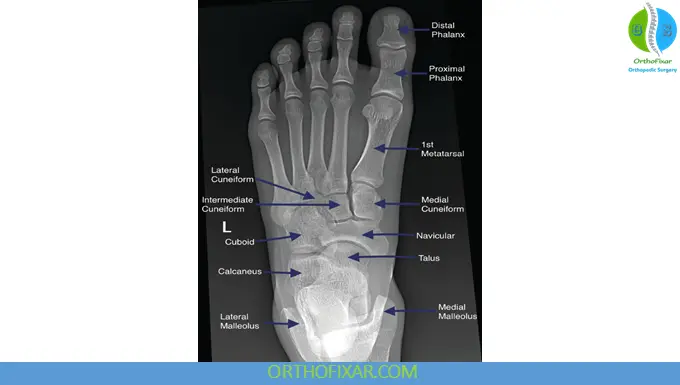

Anatomy Overview Relevant to Foot X-Ray

The foot consists of:

- Hindfoot: Talus and calcaneus

- Midfoot: Navicular, cuboid, and three cuneiform bones

- Forefoot: Metatarsals and phalanges